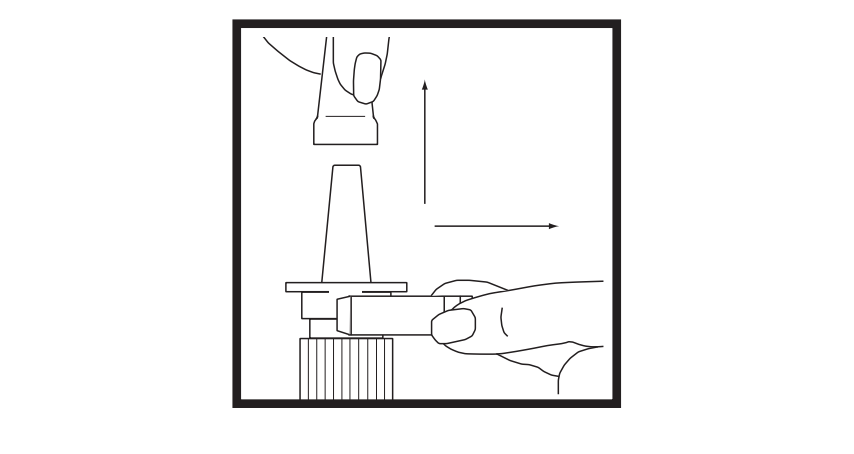

1. Remove the safety clip and the clear plastic dust cover from the spray bottle.

2. Put two fingers on the "shoulders" of the spray bottle and put your thumb on the bottom

of the bottle.

3. Hold the bottle in an upright position away from you. Apply pressure EVENLY to the

"shoulders" and push down QUICKLY AND FIRMLY until a fine spray occurs. Usually the

spray will appear after about 5 to 10 pumps.

4. The pump is now primed.

Priming only needs to be done once when you start using a new bottle of Synarel. You

will waste medication if you prime the pump before each use and will not have enough

medication for the entire treatment period.